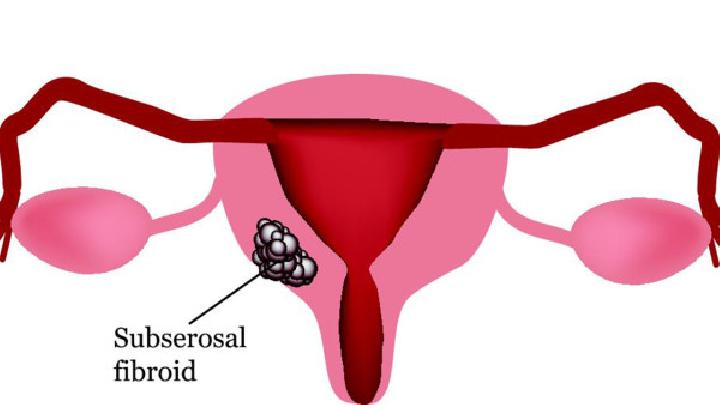

1.局部与远处复发 通常认为,远处转移是再外科手术之禁忌证。但这也不是绝对的,有一些病例可以采用新辅助治疗方法使无法切除的远处转移灶变为可以切除者,同样可以得到再次手术的机会。对存在局部多处复发患者,在有的诊疗中心可进行局部多处病灶的切除术。但因其有较高的手术死亡率,故在不具备手术经验的医院,则不宜勉为其难,可视为手术禁忌证。 对于有症状的局部多处复发患者,一般认为已无法根治性切除。姑息性手术却不能提高生存率,但仅用降低死亡率的观点来评估外科手术切除的疗效是不恰当的。有些姑息性切除可提高患者生活质量和解除其疼痛症状。为解除症状而进行的外科手术治疗只需切除大块复发的肿瘤组织。放疗联合化疗因可以解除疼痛、降低出血、提高生活质量,故通常是姑息性手术术后的常用方法。盆腔血管的选择性化疗对不可切除的肿瘤有减瘤作用。如果复发病灶接近肛门,就需要用腔内支架或结肠造口术。对有出血症状的患者,其他可选择的治疗方法还有激光消融、电烧灼和血管栓塞。局部切除对于会阴复发者,可选择腹会阴联合直肠切除术,但可导致盆腔扩散且预后不良。 3.可切除的局部复发  晚期患者包括盆腔周围侧壁肿瘤浸润、髂血管受累导致下肢水肿、双侧输尿管梗阻导致双侧肾盂积水、坐骨神经受侵犯导致双下肢肌无力、肿瘤侵犯坐骨切迹及腹主动脉周围淋巴结转移等。局限的盆腔侧壁侵犯和S2以上的骶骨侵犯,因为充分切除的可能性很小,被认为是相对禁忌证。 关于切除的信息 子宫切除手术多用于切除子宫肿瘤及某些子宫出血和附件病变等,经腹部切除子宫切除术的操作法,子宫切除术后护理很重要,因为子宫切除术不是一个太小的手术,会对身体造成一定的损伤。  任何手术,包括子宫肌瘤手术都是对患者身体有一定危害的,因此也要尽量避免。是否需要进行子宫肌瘤手术需要根据患者的实际情况来决定,这里我们就简单为您介绍一下吧。  类风湿性关节炎是一种对患者身体危害非常大的疾病,有很多患者因为多年深受这种疾病的折磨从而想到了手术切除,但是这些患者也担心切除后还会复发,所以今天就这个问题我们来了解一下,类风湿性关节炎切除后会复发吗?  女性两侧大阴唇的后面各有一黄豆大小的腺体,该腺体有长约1~2厘米的腺管,开口于小阴唇与处女膜之间的沟内,这个腺体,医学上称为“前庭大腺”。因其生理特点,前庭大腺炎切除病灶后仍然有一定的复发率,因此,保持外阴清洁是预防感染可防止复发的主要方法。  胃癌切除手术后后背经常痛怎么回事?胃癌可能会出现周围组织侵袭和转移的情况,如果出现背部疼痛的情况就要考虑可能和胃癌的脊柱转移有关,针对这种情况要及时到当地医院进行复查,根据转移的情况给予相应的治疗措施,所以胃癌是可以出现背部疼痛的。  前列腺癌睾丸切除手术多少钱,很多肿瘤晚期都会发生转移,前列腺癌也不例外。约有三分之一甚至三分之二的前列腺癌患者在初次就医时就已有淋巴结转移,多发生在骼内、骼外、腰部、腹股沟等部位。可引起相应部位的淋巴结肿大及下肢肿胀。血行转移多见于骨骼(如骨盆、骶骨、腰椎、股骨上段等〉和内脏(如肺、肝、脑、肾上腺、睾丸等)。所以患病就要及时治疗,但是很多人不知道前列腺癌治疗要花多少钱,下面就由小编详细的为您介绍,前列腺癌睾丸切除手术多少钱。  骨癌切除后还会复发吗?部分骨癌患者在手术后还会出现病情恶化或者复发的情况,患者很不明白这是怎么回事,骨癌复发对人体的危害很大,因此要注意预防,这对治疗效果有很大的帮助,而且还能让患者摆脱骨癌的困扰,和正常人一样生活。  近几年胆囊息肉的患者越来越多,据临床统计显示,其中产生癌变的大约有12%,所以为了预防胆囊息肉发生癌变,患者们一定要积极进行治疗。目前胆囊息肉最有效的治疗方法当属手术治疗,手术可分为保胆取息和胆囊切除两种方式,由于胆囊切除多少会对身体产生一些不利影响,并且不是所有患者都需要行胆囊切除术,因此患者们一定要三思而后行。  有时候,人们在进行疾病治疗方面,对于引起该类疾病的原因是模糊的,因此在治疗方面不能很好地展开。对于子宫肌瘤此类常见妇科疾病,广大女性朋友也不是很清楚其病因,在治疗方面也是比较困难的,下面小编就为大家介绍子宫肌瘤是怎么引起的?  肝癌是如今世界上对人类健康危害最大的恶性肿瘤之一,对于早期肝癌病人和病人家属来说,希望明确的第一个问题就是:肝癌早期切除后能治愈吗?就目前治疗现状而言,肝癌仍然是医学上未被攻克的一大难题,然而这也并不等于得了肝癌就被宣判了死刑,临床上亦有许多治疗后长期生存的病例。 |